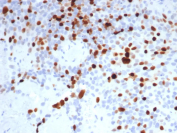

Topoisomerase II alpha Antibody Lymph Node IHC. Immunohistochemical analysis of DNA Topoisomerase II alpha (TOP2A) in formalin-fixed, paraffin-embedded human lymph node tissue using Topoisomerase II alpha antibody clone TOP2A/8103R. Strong nuclear HRP-DAB brown staining is observed in proliferating lymphocytes, with enrichment in germinal center regions, consistent with elevated expression during active cell division. HIER: boil tissue sections in pH 9 Tris-EDTA buffer for 20 min followed by cooling prior to staining.

Topoisomerase II alpha antibody, also referred to as TOP2A antibody and DNA topoisomerase II alpha antibody, recognizes a protein that localizes predominantly to the nucleus, consistent with its role in DNA metabolism and chromosomal dynamics. Immunohistochemistry analysis of formalin-fixed, paraffin-embedded human lymph node tissue demonstrates strong nuclear HRP-DAB brown staining in proliferating lymphoid cells, with particularly intense signal in germinal center lymphocytes. These regions represent zones of rapid clonal expansion and DNA replication, and the enriched nuclear staining pattern reflects the elevated expression of TOP2A in cells undergoing active cell cycle progression. The sharp contrast between strongly positive germinal centers and less proliferative surrounding regions provides a clear and biologically meaningful staining pattern for tissue-based analysis.

Functionally, TOP2A expression is tightly regulated throughout the cell cycle, with peak levels observed during S phase and G2/M phases when DNA replication and chromosome segregation occur. Its expression is therefore closely associated with proliferative activity and is widely used as a marker of actively dividing cells in both normal and cancer tissues. In IHC, this biology is reflected by strong nuclear staining in proliferative compartments such as germinal centers, tumor cell populations, and other rapidly cycling cell types, while quiescent or differentiated cells exhibit lower levels of expression. This dynamic expression pattern makes TOP2A particularly useful for identifying regions of active cell division within complex tissue architectures.